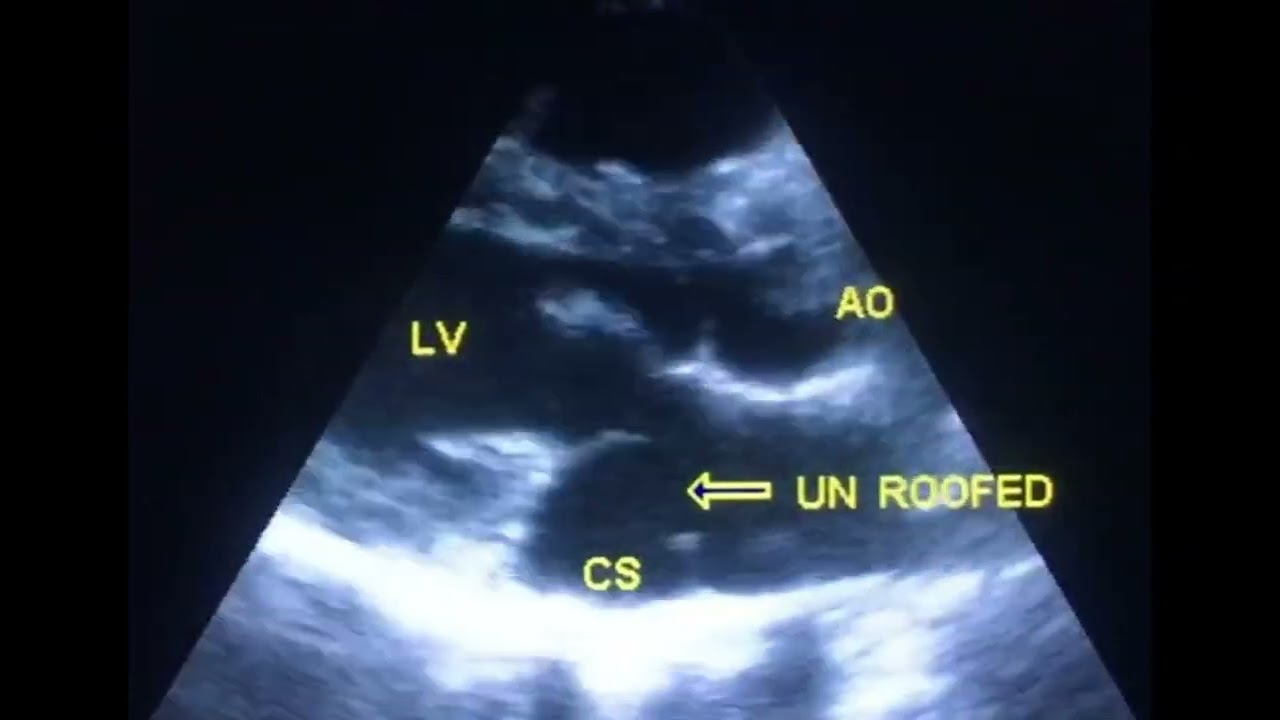

How to diagnose unroofed coronary sinus by echo

Unroofed coronary sinus echoUnroofed coronary sinus echocardiographyUnroofed coronary sinus and persistent left SVCUnroofed coronary sinus contrast echocardiographyUnroofed coronary sinus contrast echo

Unroofed coronary sinus is the rarest form of ASD and is too difficult to diagnose by echo.

It is often associated with persistent left SVC, so injection of agitated saline in the vein of left upper extremity will opacified coronary sinus and its defected will be appeared.